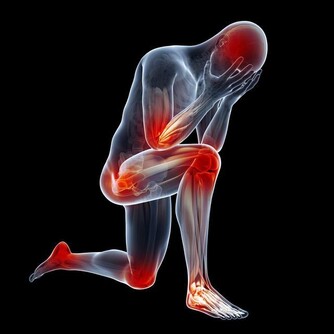

1、利用休息和活動的時間加強身體的血液循環,消除局部肌肉疲勞,這樣對頸椎病的治療有幫助,而且也能預防和緩解頸椎的勞損。

2、生活習慣:在運動的時候,一定要防止劇烈的活動扭傷或是拉傷頸椎,睡覺時候的習慣不良或枕頭原因造成的落枕也會加重此病。

3、在生活中就要注意頸椎的保暖,不要讓頸椎處於電扇、空調等低溫條件下,不然更容易發病哦!